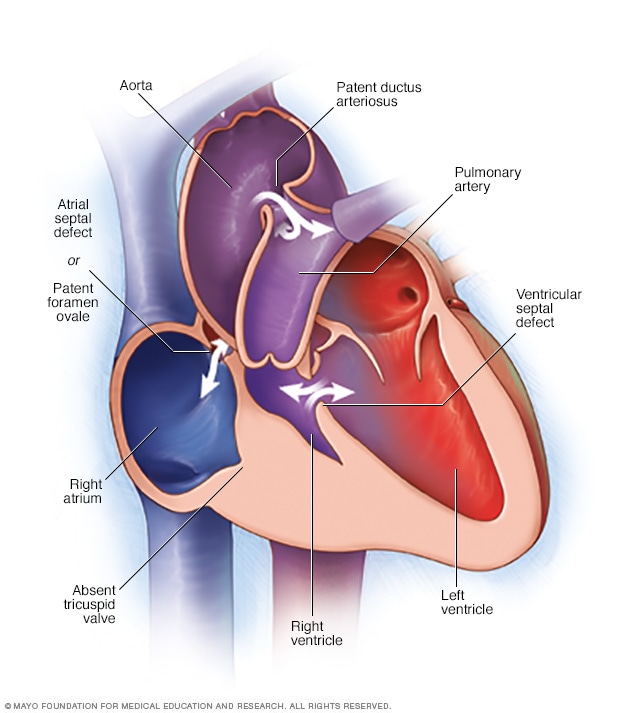

Cone Reconstruction For Ebstein Anomaly Mayo Clinic

Cone Reconstruction For Ebstein Anomaly Mayo Clinic

Tricuspid Atresia Symptoms And Causes Mayo Clinic

Tricuspid Atresia Symptoms And Causes Mayo Clinic